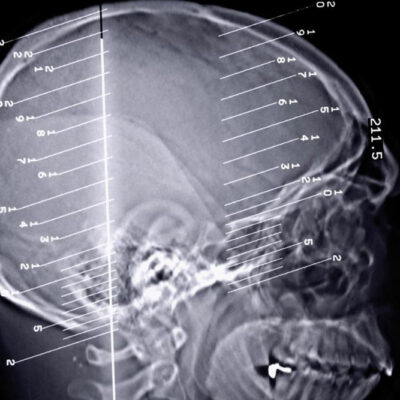

The human body can perform all its functions seamlessly when every organ of the body works in unison to perform the task. A slight change in the functions of the organ can disrupt the entire functioning of the body. Epilepsy seizures are a kind of disorder that occurs when we there is a problem in our brain’s electrical system.

Almost any disorder that ails us can be treated. Being an earthling in the 21st century comes with its added benefits. Anything that affects us or interferes with the normal functioning of our bodies can be treated effectively. They don’t survive an onslaught of effective medications and succumb to it finally and thus, you can say “good riddance to bad rubbish.” Epilepsy is a neurological condition that causes a sudden surge of electrical impulses in the brain, which cause epilepsy seizures symptoms to surface.

Epilepsy is a dreaded disorder, especially since it is connected to the dysfunctioning of the brain. The brain plays a pivotal role in the functioning of the human body and any kind of issue can lead to severe complications. The disorder is related to the dysfunctioning of the central nervous system in the brain.

Epilepsy not only causes physical trauma but can also cause seizures that make living a normal lifestyle difficult. Epilepsy is a condition in which the brain’s nervous system does not function in a normal manner. This means that the central nerve in the brain gives out wrong signal to the body.

Individuals who suffer from epilepsy are at the receiving end of physical as well as emotional trauma. The condition is one that can take the person’s life into turmoil. It is a disease that affects the central nervous system of the brain. Thus, causing the nerve cells give out wrong signals to the body.

Epilepsy is a disorder of the brain that has consequences wherein a person suffers from seizures and periods of unusual behavior. It is particularly the disruption of the functioning of the nerve cell activity in the brain and can also lead to a loss of consciousness for long periods of time.